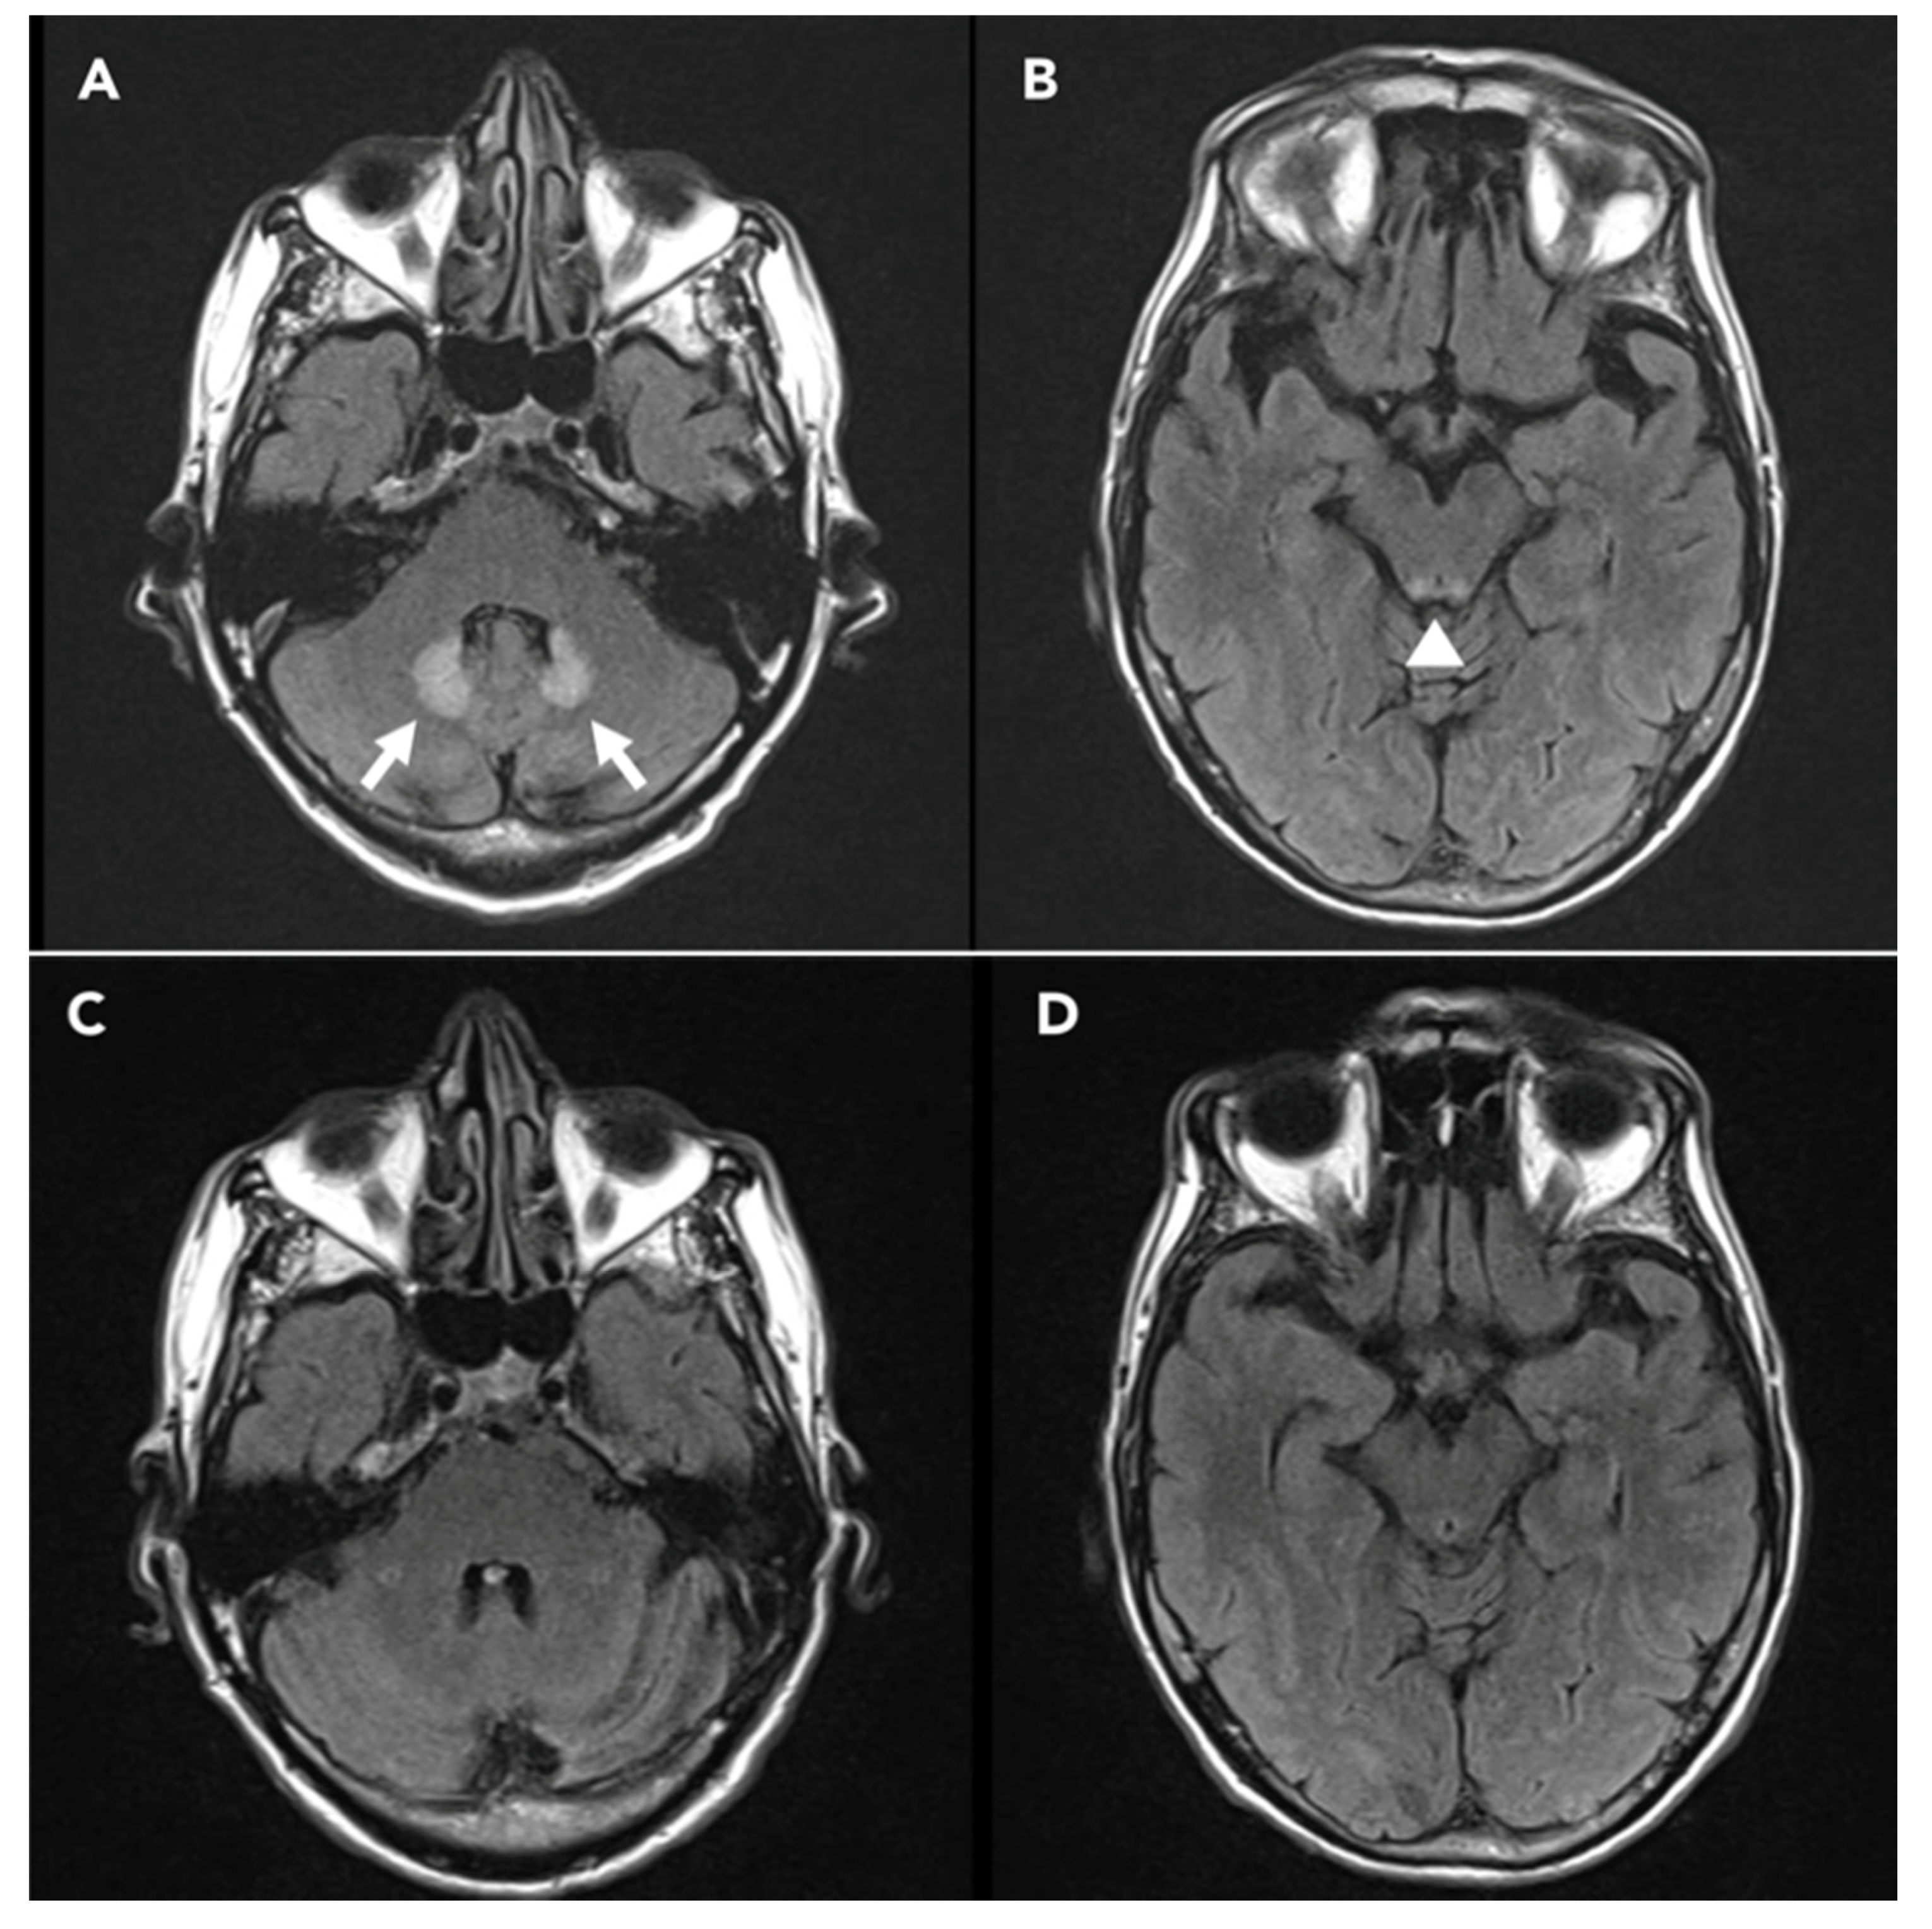

| Ferroir et al. 2009 [12] | 76, M | 45 | Peripheral Neuropathy, Cerebellar syndrome, focal to bilateral tonic clonic seizures. | T2 FLAIR hyperintensity in bilateral dentate nucleus, thalamus, splenium of corpus callosum. | Normal (NOT SHOWN) | Not done | Resolution |

| Groothoff et al. 2010 [13] | 38, F | 132 | Cerebellar syndrome, altered mental status, focal to bilateral tonic clonic seizures. | Abnormal signal in T2 FLAIR in the centrum semiovale and cerebellar peduncles. | Unspecific encephalopathy findings (NOT SHOWN) | Unchanged | Death |

| Cantador et al. 2013 [14] | 56, M | 5 | NCSE † | Hyperintense lesion of the dentate nucleus, middle cerebellar peduncles, olivary nuclei and corpus callosum in FLAIR sequences. | GPDs ‡ | Normalization | Resolution |

| Hobbs et al,.2015 [15] | 65, F | 33 | Confusion and disorientation. | Symmetrical T2 hyperintensity and generally restricted diffusion in bilateral dentate nuclei, corpus callosum, midbrain, superior cerebellar peduncles, internal capsules, and cerebral white matter. | Diffuse slowing, focal left fronto-central slowing, epileptiform sharp waves at left fronto-central (NOT SHOWN) | Unchanged | Coma and Death |

| Wang et al. 2017 [17] | 58, F | 94.5 | Rapidly progressive consciousness disturbance with vegetative state. | Abnormal high signals in T2 FLAIR at bilateral dentate nuclei of the cerebellum, midbrain and dorsal pons and restricted diffusion in bilateral periventricular white matter, anterior and posterior splenium of corpus callosum. | Generalized high-voltage sharp wave complexes in quasi-periodic patterns with TM **. | Slow background activity at theta range | Unchanged |

| Sørensen et al. 2018 [18] | 66, F | 78 | Cerebellar syndrome, focal to bilateral TC seizures, multifocal myoclonus. | Abnormal T2 FLAIR hyperintense signal changes in the bilateral dentate nuclei. | Normal (NOT SHOWN) | Not done | Resolution |